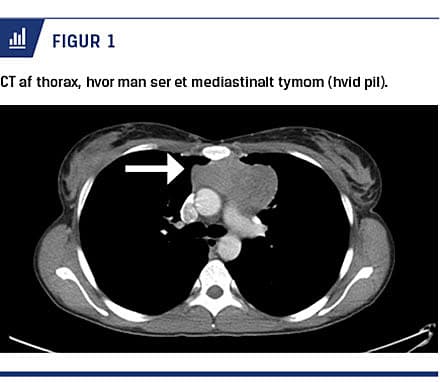

Hos en tidligere rask 33-årig kvinde udvikledes der over fem uger progredierende svær, primært proksimal svaghed og udtrætning i arme og ben, ansigts- og halssvaghed samt udtalt synkebesvær. Der var ingen autonome symptomer, og senereflekserne var normale. Med baggrund i forhøjet kreatinkinaseniveau (2.700 E/l) og elektromyografiforandringer fik man mistanke om polymyositis, hvorfor der blev bestilt muskelbiopsi. En CT af thorax viste en 8 × 8 × 8 cm tymomsuspekt forandring i mediastinum (Figur 1), der ved efterfølgende biopsi kunne klassificeres histologisk som malignt tymom (WHO type B2/B3). Polymyositisdiagnosen blev bekræftet ved muskelbiopsi, som viste invasion af CD8+-positive lymfocytter i muskelfibrene (Figur 2). Ved en helkrops-PET/CT udelukkede man anden malignitet end tymom. Den kliniske tilstand vakte også mistanke om myasteni. Denne diagnose bekræftedes ved tilstedeværelse af forhøjet AChRab-titer (66 nmol/l). Patienten led således af både polymyositis og myasteni.